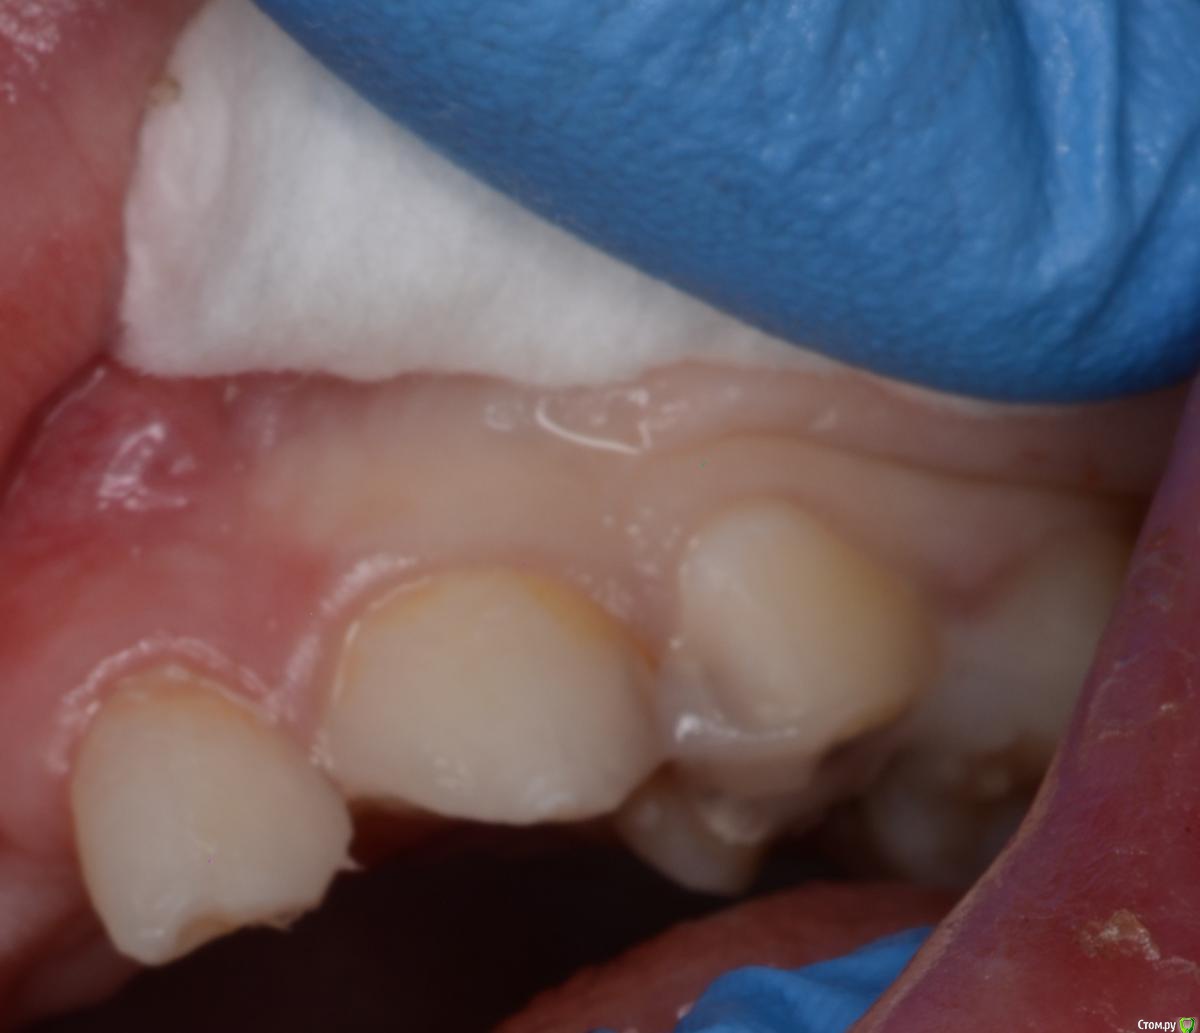

CRAZYDUCK Опубликовано 21 февраля, 2020 Автор Поделиться Опубликовано 21 февраля, 2020 Почему-то не по порядку фото грузятся . Ребёнок 4 года , ранее был опыт лечения в наркозе , 7.5 восстановлен окклюзионно и вестибулярно , 7.4 окклюзионно . На фото «до» видно налёт в пришеечной зоне . Восстановила коронками в ЗакС 1 Ссылка на комментарий

CRAZYDUCK Опубликовано 11 февраля, 2020 Автор Поделиться Опубликовано 11 февраля, 2020 Лечение 3.6 , 7.5 Обратите внимание на десну дистально на 3.6 . Ее можно заправить флоссом и платком 4 Ссылка на комментарий